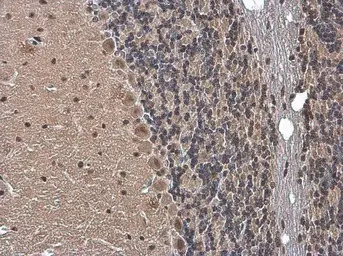

Gemin 5 antibody detects Gemin 5 protein at cytoplasm and nucleus by immunohistochemical analysis.

Sample: Paraffin-embedded mouse brain.

Gemin 5 stained by Gemin 5 antibody (GTX130498) diluted at 1:500.

Antigen Retrieval: Citrate buffer, pH 6.0, 15 min